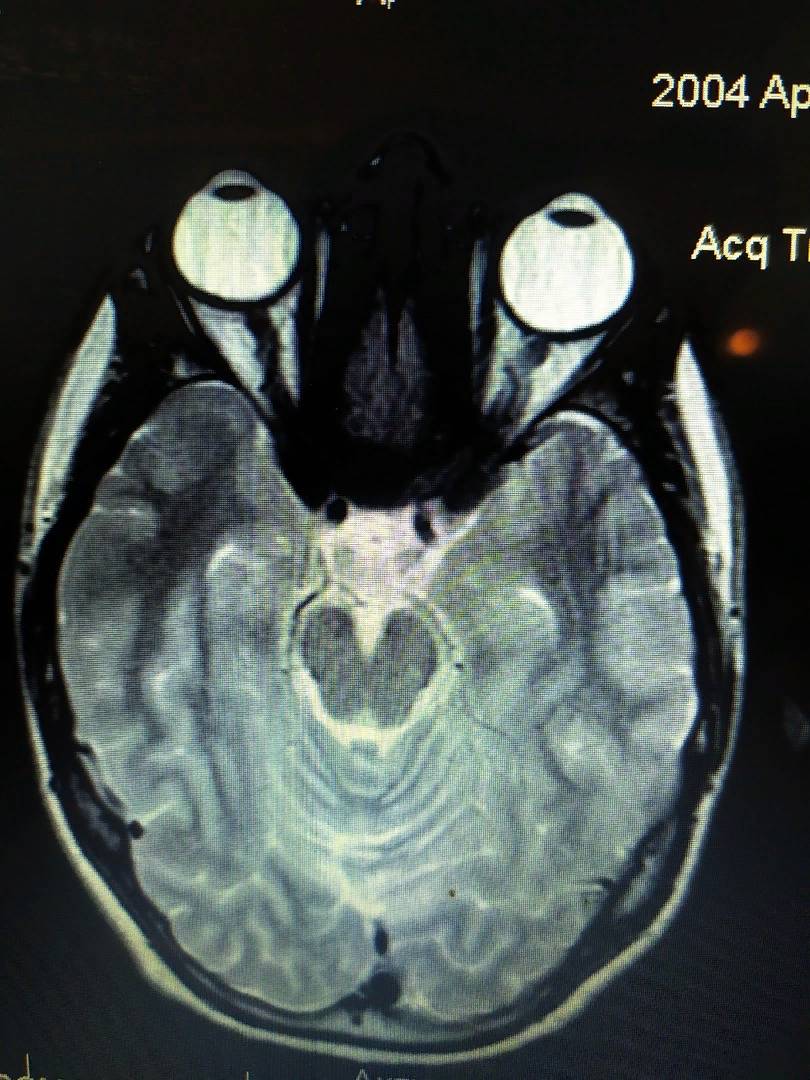

Если вы до сих пор не осознали реальной картины, посмотрите на следующее фото:

Ещё одна томография, которую мне прислал мой подписчик. Обратите внимание на то, что правый глаз заметно, но не сильно больше левого.

На правом глазу здесь -6.25 диоптрий. А на левом -4.5. Видите, разница не сильно большая, поэтому и глаза в длину не сильно отличаются (по сравнению с первой фотографией).

И опять заметьте, что глаза здесь не сдавлены глазодвигательными мышцами с боков. А они просто выросли и стали больше.